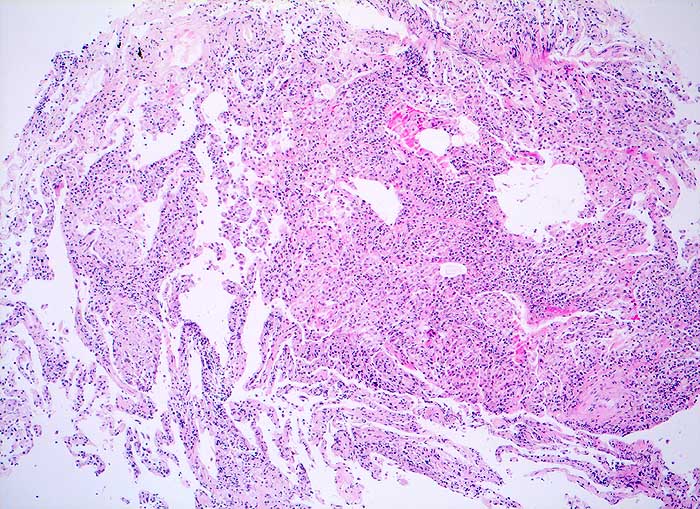

Alveoläres Lungengewebe mit mässig bis deutlich ausgeprägter interstitieller Entzündung und einigen lockeren intraalveolären Granulomen. Herdförmige geringe interstitielle Fibrose. Geringe Alveolarzellretention.

Broncho-alveoläre Lavage: Massive Lymphozytose und deutliche Vermehrung der Alveolarmakrophagen mit schaumzelliger Umwandlung. Mässige Eosinophilie und deutliche Vermehrung der Mastzellen.

Die Vermehrung der Alveolarmakrophagen mit schaumzelliger Umwandlung in der BAL passt zu dem hier histologisch beobachteten Befund der Alveolarzellretention, was bei der exogen-allergischen Alveolitis häufig zu beobachten ist.